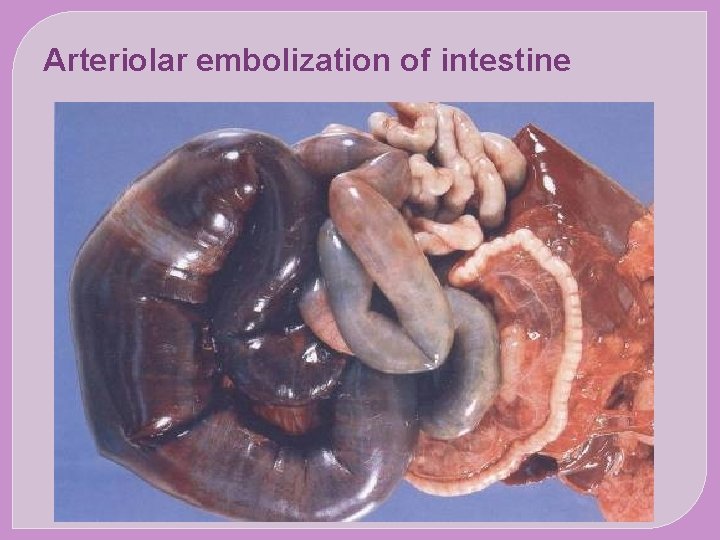

�The major sites for arteriolar embolization are �the lower extremities (75%) and �the brain (10%), �with the intestines, kidneys, and spleen affected to a lesser extent. �The consequences of embolization in a tissue depend on vulnerability to ischemia, caliber of the occluded vessel, and the collateral blood supply; �in general, arterial embolization causes infarction of the affected tissues.

SYSTEMIC EMBOLISM The origin of emboli: Most arise from intracardiac mural thrombi or from ulcerated atherosclerotic plaques The sequel: Arteriolar embolization (e. g. the brain, kidneys , spleen and intesrines)

Arteriolar embolization of intestine